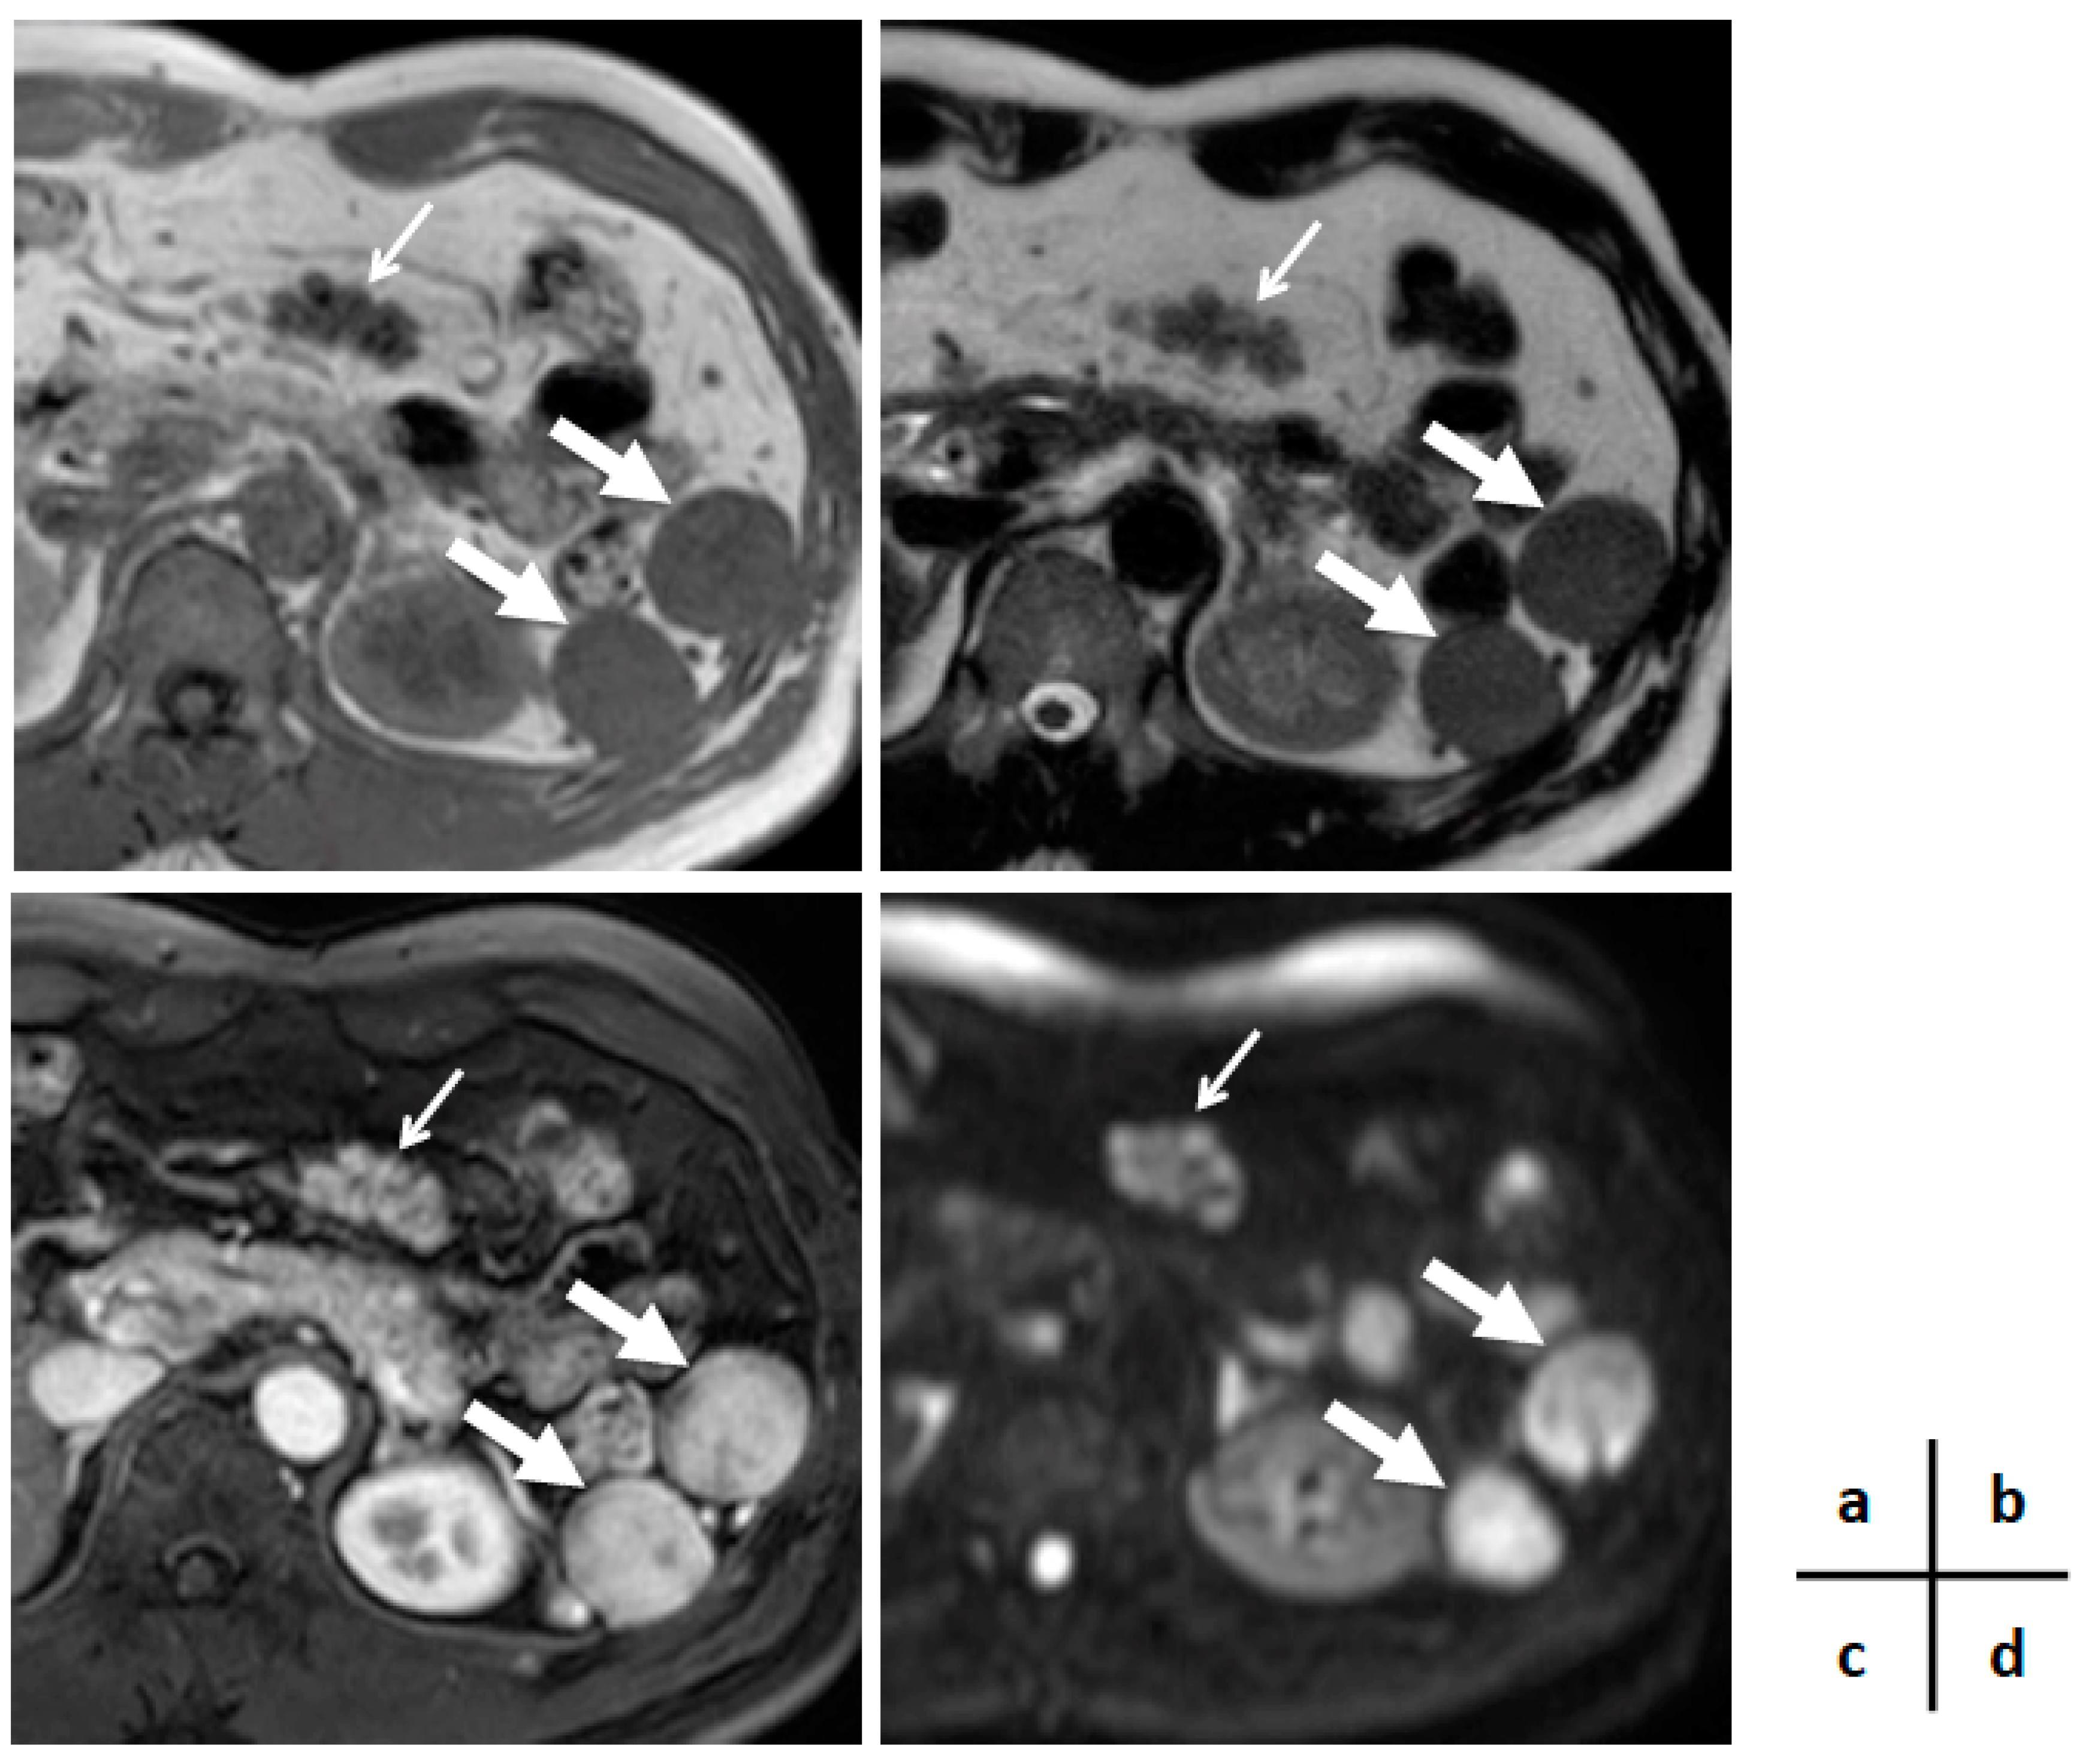

A Multinodular Mass of Abdominal Splenosis: Case Report of Uncommon Images of a Rare Disease

2. Case Presentation